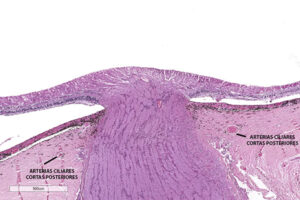

La vascularización del nervio óptico comprende un sistema que se encarga de la parte periférica del nervio y otro, de la porción central del nervio. El sistema periaxial deriva de

En la región de la lámina cribosa y cabeza de nervio óptico hay una red capilar extensa derivada del círculo arterial de Zinn-Haller que se encuentra formado por las arterias